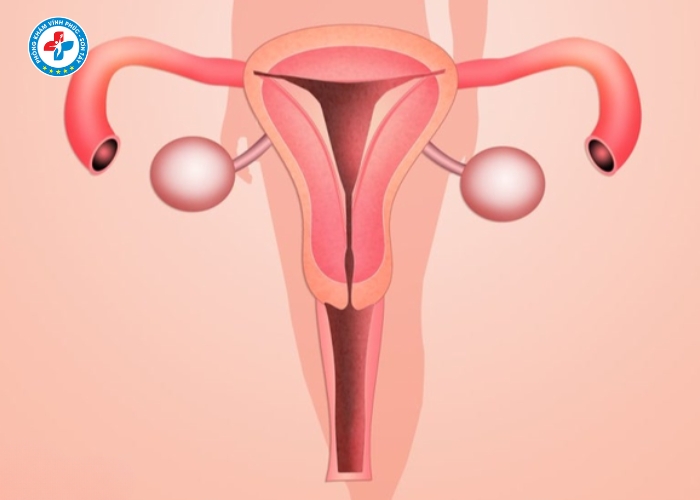

Lộ tuyến cổ tử cung là gì?

Lộ tuyến cổ tử cung là tình trạng các tế bào tuyến bên trong cổ tử cung phát triển và xâm lấn ra mặt ngoài cổ tử cung. Những tế bào này tiết dịch nhiều hơn bình thường, tạo môi trường thuận lợi cho vi khuẩn phát triển.